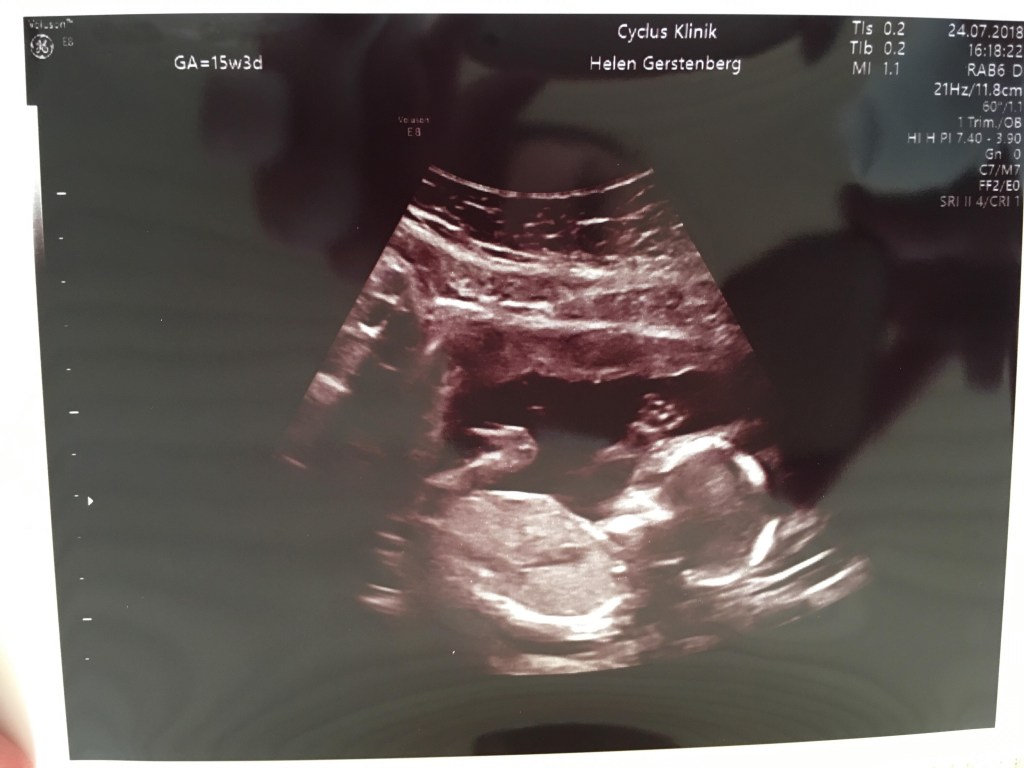

Jeg var meget utålmodig og ville gerne se min lille baby og dens hjerteblink. Martin var derimod mere rolig. Heldigvis fik jeg ham overtalt til at vi fik en såkaldt “tryghedsscanning” i uge 9 på en privat klinik. Jeg kunne simpelthen ikke vente længere. Jeg måtte bare vide at alt var godt. Eller om alt var godt..

Vi kom ind gennem en meget gammel port på Gothersgade. De gamle små mørkebrune trætrin knirkede under os, da vi langsomt gik op mod klinikkens dør. Martin gik forrest og en smilende kvinde tog imod os, da vi kom ind. En anden kvinde styrtede rundt og spurgte på vejen ind i et rum, om det var mig der var Elisabeth. Jeg nikkede og hun sagde “To minutter, så skal jeg være der”. Hun var inde i rummet et stykke tid, kom ud igen, smilede til os, mens hun hastigt hentede en stor vase med blomster, som hun satte ind i rummet. “Nu kan I bare komme ind” sagde hun. Vi trådte ind og der var meget større end jeg havde forventet. I den ene side stod en stor briks. Ved siden af var der placeret en stor indbydende lænestol med en pude i. Blomsterne i vasen stod på et bord op ad de gamle sprossede vinduer, og da kvinden så at jeg kiggede på dem, smilede hun og sagde “Ja, det går jo ikke at her ikke er hyggeligt, når I skal se jeres baby for første gang”. Det føltes som om at de begge kendte os i forvejen og nærmest havde glædet sig til, eller ligefrem ventet på, at vi skulle komme ind på deres klinik.

Selvom det var første gang jeg nogensinde skulle have en ultralydsscanning og se et barn i min mave, føltes det som det mest naturlige i verden. Jeg lagde mig til rette på briksen, trak lidt ned i mine cowboybukser og Martin satte sig i den store lænestol ved siden af og tog min hånd. For enden af briksen var en stor skærm, hvor vi kunne følge med i scanningen. Hun advarede mig om det kolde gele og smurte min mave forsigtigt ind, inden hun satte scanneren på. Og lige dér lå vores lille vidunder. Den lillebitte baby lå på siden med ryggen mod os, så vi kunne se den søde numse og de små ben, som han havde trukket op under sig. (På det tidspunkt vidste vi selvfølgelig intet om at det var en lille dreng der lå derinde og moonede til os).

I 10 minutter holdt vi i hånden og kiggede bare på en kidneybønne, der boblede rundt. En kidneybønne, der dengang var 9+4 uger gammel. Da vi var færdige tørrede hun geléen af min mave med et lille varmt håndklæde. Hun trykkede os begge i hånden og sagde tillykke med vores fine lille baby, før hun forlod rummet og gav os god tid til at samle vores ting.

Da vi kom ud til skranken lå en fin lyselilla mappe klar med dokumenter, der indeholdte al information fra scanningen. Der var målene på vores baby, mit navn og cpr-nummer og nogle andre ting, som jeg ikke helt vidste hvad var. Der var også nogle postkort, men vigtigst af alt, var scanningsbillederne og et link, hvor vi kunne se en video af vores lille baby-Blob boble rundt i min mave. Den video så jeg på flere gange de næste mange uger, hver gang jeg savnede et glimt ind i maven.